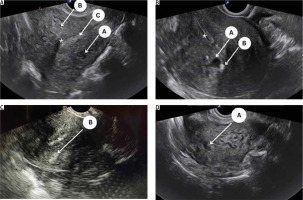

All eligible women underwent a detailed 2D-TVS with grey scale and power Doppler during the secretory phase of the menstrual cycle. All TVS were performed by 2 experienced sonographers (SJ and US) who were blinded to the patient’s clinical symptoms. A thorough evaluation of the pelvis was performed including the uterus (myometrium, endometrium, and junctional zone), bilateral adnexa, anterior and posterior compartment, rectum, bladder, rectosigmoid junction, presence of adhesion (sliding signs), site-specific tenderness, and translesional vascularity. Women with features of endometriosis (endometrioma or deep endometriotic nodule) or myoma were excluded from the study. A diagnosis of adenomyosis was established if one direct MUSA feature or one indirect MUSA feature with involvement of junctional zone was observed [9]. Direct features included were as follows: cysts in the myometrium; hyperechogenic islands; and echogenic subendometrial lines or buds (Fig. 1). Indirect features included those secondary to the presence of endometrial tissue in the myometrium, such as globular uterus, asymmetrical myometrial thickening, fan-shaped shadowing, translesional vascularity, irregular junctional zone, and interrupted junctional zone (Fig. 2). Adenomyosis was defined as diffuse if < 25% of the lesion was surrounded by normal myometrium, provided that > 25% of the entire myometrium was involved, and focal if > 25% of the lesion surrounded by normal myometrium [7].